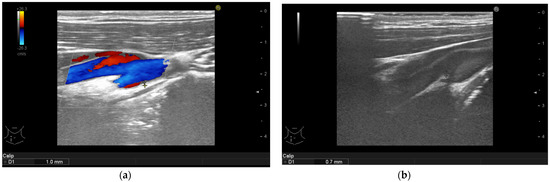

3.4. Ultrasonographic Findings

| Arterial Intima Media Thickness | Baseline Median (IQR)  | 6-Month Follow-Up Median (IQR) | p-Value |

| Intima media thickness of the right carotid arteries (mm) | 1.1 (1.0–1.3) | 0.8 (0.6–0.9) | <0.001 |

| Intima media thickness of the left carotid arteries (mm) | 1.1 (0.9–1.35) | 0.7 (0.6–0.9) | <0.001 |

| Intima media thickness of the right brachial arteries (mm) | 0.75 (0.6–0.9) | 0.6 (0.5–0.7) | <0.001 |

| Intima media thickness of the left brachial arteries (mm) | 0.8 (0.6–0.9) | 0.5 (0.5–0.7) | <0.001 |

| Intima media thickness of the right femoral arteries (mm) | 0.9 (0.8–1.05) | 0.7 (0.5–0.9) | <0.001 |

| Intima media thickness of the left femoral arteries (mm) | 0.8 (0.6–1.1) | 0.7 (0.5–0.8) | <0.001 |